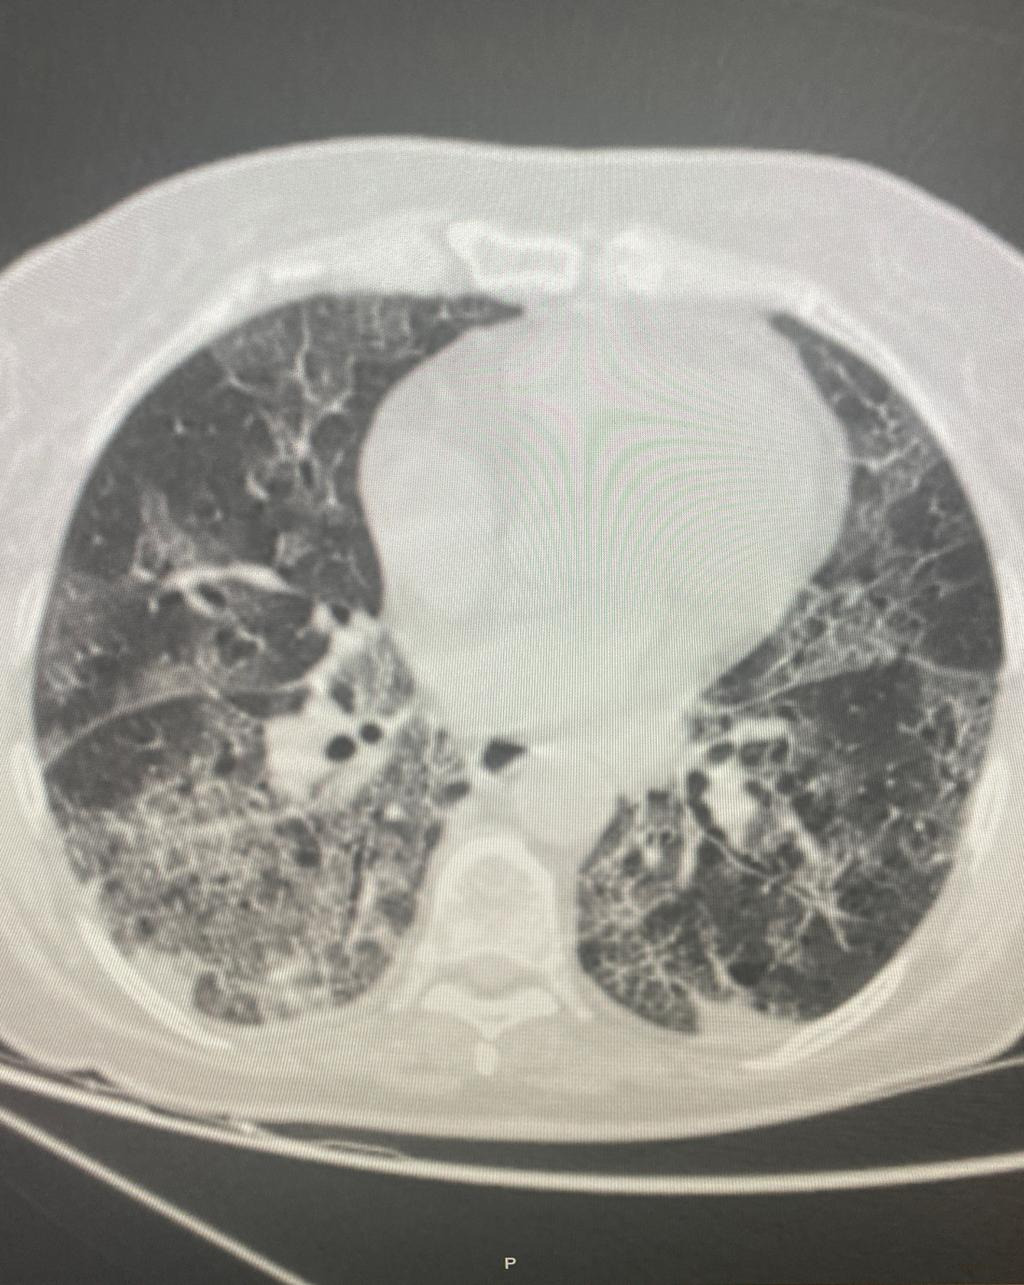

https://adsense.google.com/adsense/u/1/pub-9161951367286286/myads/sites/preview?url=notion6988.tistory.com ⚠️ ‘중증’ 코로나 환자, 폐 상태 확인했더니… ‘무서운 경고’